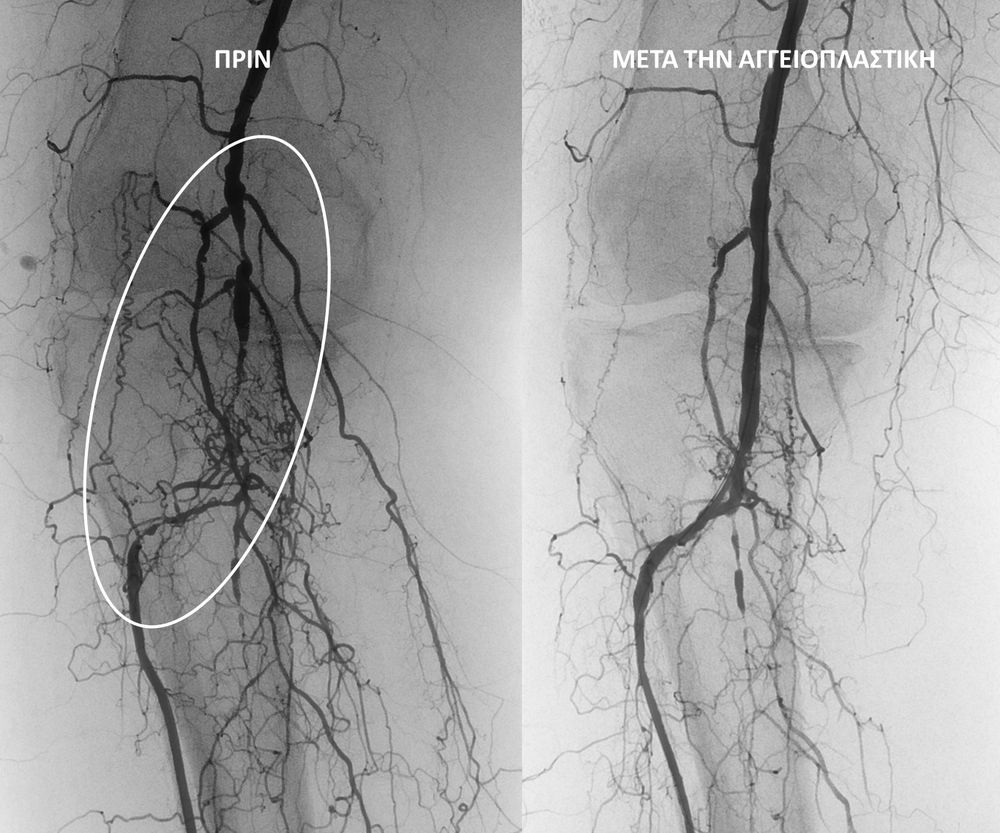

O σακχαρώδης διαβήτης είναι μεταβολική ασθένεια η οποία χαρακτηρίζεται από αύξηση της συγκέντρωσης του σακχάρου στο αίμα (υπεργλυκαιμία) και διαταραχή του μεταβολισμού της γλυκόζης. Ο βαθμός αύξησης της γλυκόζης στο αίμα και η παραμονή των αυξημένων τιμών της για μεγάλο χρονικό διάστημα βλάπτουν, κυρίως, τα μικρά αγγεία, προκαλώντας διαβητική νευροπάθεια, διαβητική νεφροπάθεια, αμφιβληστροειδοπάθεια κ.τ.λ., με σοβαρότατες συνέπειες σε πολλά όργανα-συστήματα.Στην Ελλάδα κάθε χρόνο πραγματοποιούνται 2.000 – 3.000 ακρωτηριασμοί κάτω άκρων, αφού το 4-5% των πασχόντων από διαβήτη εμφανίζει περιφερική αγγειοπάθεια με έλκη ή και γάγγραινα στα πόδια. Σε ποσοστό 80% οι ακρωτηριασμοί θα μπορούσαν να αποφευχθούν και η επεμβατική ακτινολογία μπορεί να βοηθήσει σημαντικά.Η διαδερμική ενδαγγειακή αγγειοπλαστική (percutaneous transluminal angioplasty, PTA) είναι μια ελάχιστα επεμβατική μέθοδος αντιμετώπισης των αρτηριακών στενώσεων ή και αποφράξεων του διαβητικού ποδιού (περιφερικήδιαβητικήαρτηριοπάθεια).